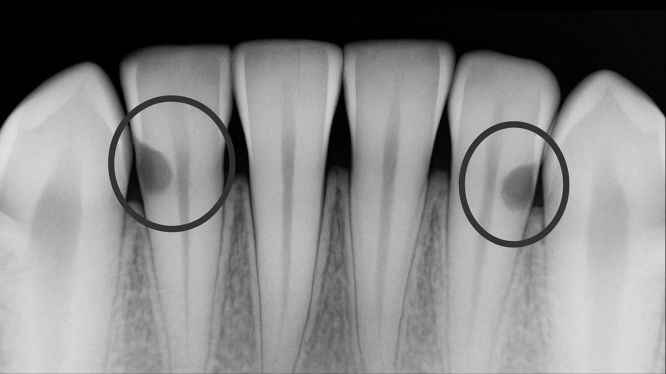

📸 4. La verdad que solo la tecnología revela: radiografías digitales

Aquí viene la parte más importante:

👉 No hay forma humana de ver una caries interproximal sin radiografías.

Ni el espejo dental, ni la luz, ni el ojo más entrenado.

💡 La radiografía es la única herramienta que permite ver lo que está pasando entre los dientes.

💡 6. Las radiografías detectan hasta lesiones del tamaño de una semilla

Algo imposible de ver con la vista humana.